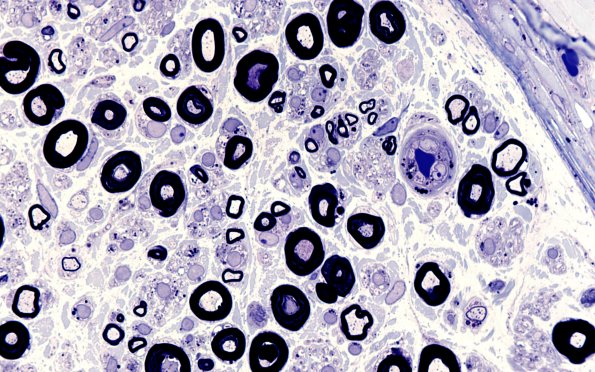

Washington University Experience | PERIPHERAL NEUROPATHY | 17 TOXIC NEUROPATHIES | Amiodarone | 2A8 Amiodarone (Case 2) Plastic 100X 4

2A8,9 Osmiophilic inclusions are seen in the vessels (arrow, 2A9), Schwann cells and perineurium. (plastic section)